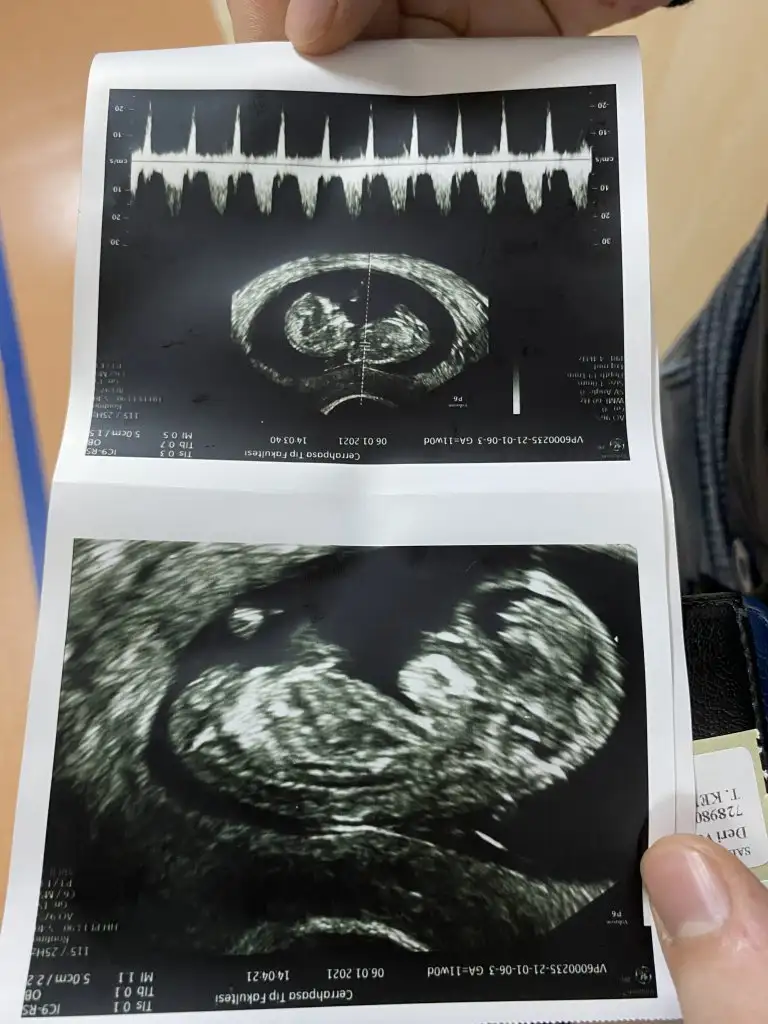

Sana yazacaktım msjı bulamadım benim yorumum bebek erkek nub teorisinde çıkıntı yukardaArkadaşlar 12. Haftada detaylı ultrasonda doktorum erkek dedi genitalin resminide çekti 14. Haftamdayım başka bir doktor kemik yapısına göre kız dedi tecrübeli arkadaşlar bakabilir mişne olsa bizim ama merak resimler 12 ve 14 hafta resimleri

benimde 12 haftalık böyle bir çıkıntı var dr erkek dedi size ne söylediBanada cinsiyet tahmininde bulunabilir misininz Eki Görüntüle 2781088

10 +4 haftalik hamileyim doktor erkek dedi ama emin olamadik.Yorum yapabilecek olan varmi.

Bu görüntüye göre kesin kız bebek dedi kardeşim. Ben anlamıyorum ama kızkardeşim bu işin erbabıAma 12 haftaya kadar degişiklik gösterebiliyormuş. 12 haftadan sonra tekrar resim atarsanız tekrar bakabilir.